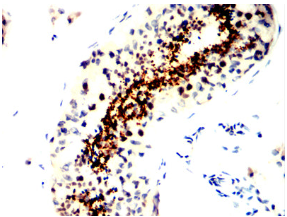

SPATA19 Mouse Monoclonal antibody[4A9F9]

Immunogen:    Purified recombinant fragment of human SPATA19 (AA: 25-167) expressed in E. Coli.

IHC    1/200 - 1/1000